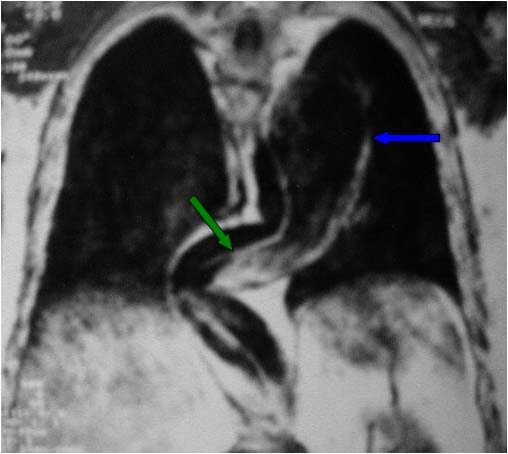

SIGNO DEL COLGAJO (O FLAP) INTIMAL

Signo de disección aórtica que puede verse tanto en ecografía, TC, resonancia magnética y arteriografía. Consiste en la presencia de una lámina -la capa íntima de la pared aórtica disecada- en el interior de la luz aórtica. En la imagen vemos un estudio de angioTC que muestra el colgajo tanto en la aorta ascendente como en la descendente. Puede distinguirse perfectamente la luz verdadera (más contrastada) de la falsa (menos densa).

Otro ejemplo del signo (flecha) en el que es más difícil diferenciar la luz verdadera de la falsa. A la izquierda del flap vemos una zona menos densa, es decir, se trata de la luz falsa.

Corte coronal de resonancia magnética de tórax que muestra un aneurisma de la aorta torácica (flecha azul) con disección de la íntima (flecha verde).